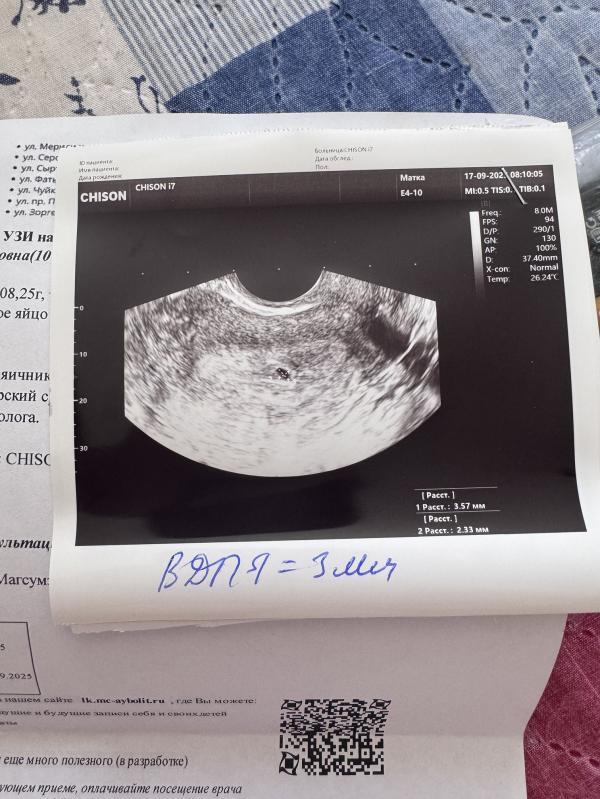

Сказали что 4 по ак, свои 2, через месяц сказали придти на узи чтобы послушать сердцебиение